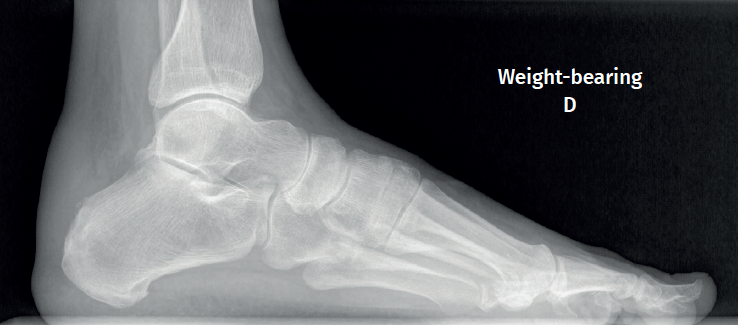

Approximately 6% of the general population will experience some pain episode of the Achilles tendon during life(1). Of these patients, approximately one-third will present tendon insertion damage(2,3). Patients with insertional tendinopathy of the Achilles tendon (ITA) typically experience pain and functional limitation, aggravated by physical activity and following resting periods. They may present thickening of the insertional portion of the tendon, most often at the lateral margin (Figure 1).

Figure 1. Insertional tendinopathy of the Achilles tendon. Thickening of the soft tissues, prominence on the external side.